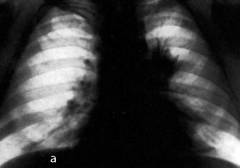

Лучевая диагностика рака легких критически важна для раннего выявления заболевания. На рентгеновских снимках можно увидеть тени различного размера, формы и интенсивности. Основной признак злокачественной опухоли — неровная поверхность и лучистые контуры.

В зависимости от рентгенологической картины выделяют следующие типы рака легких:

- центральный рак (изображение А);

- периферический рак (узловая, пневмониеподобная, плевральная, полостная формы) (изображение Б);

- медиастинальный рак (изображение В);

- верхушечный рак (изображение Г).